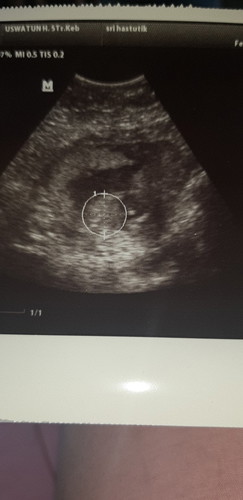

Bunda ada yg bisa baca hasil usg ini

foto usg nya yg full coba bun, biasanya ada keterangan tulisan disampingnya. Oh iya itu yg usg dokter atau bidan bun?

Ada keterangannya nggak? GA GS EDD dan sebagainya...